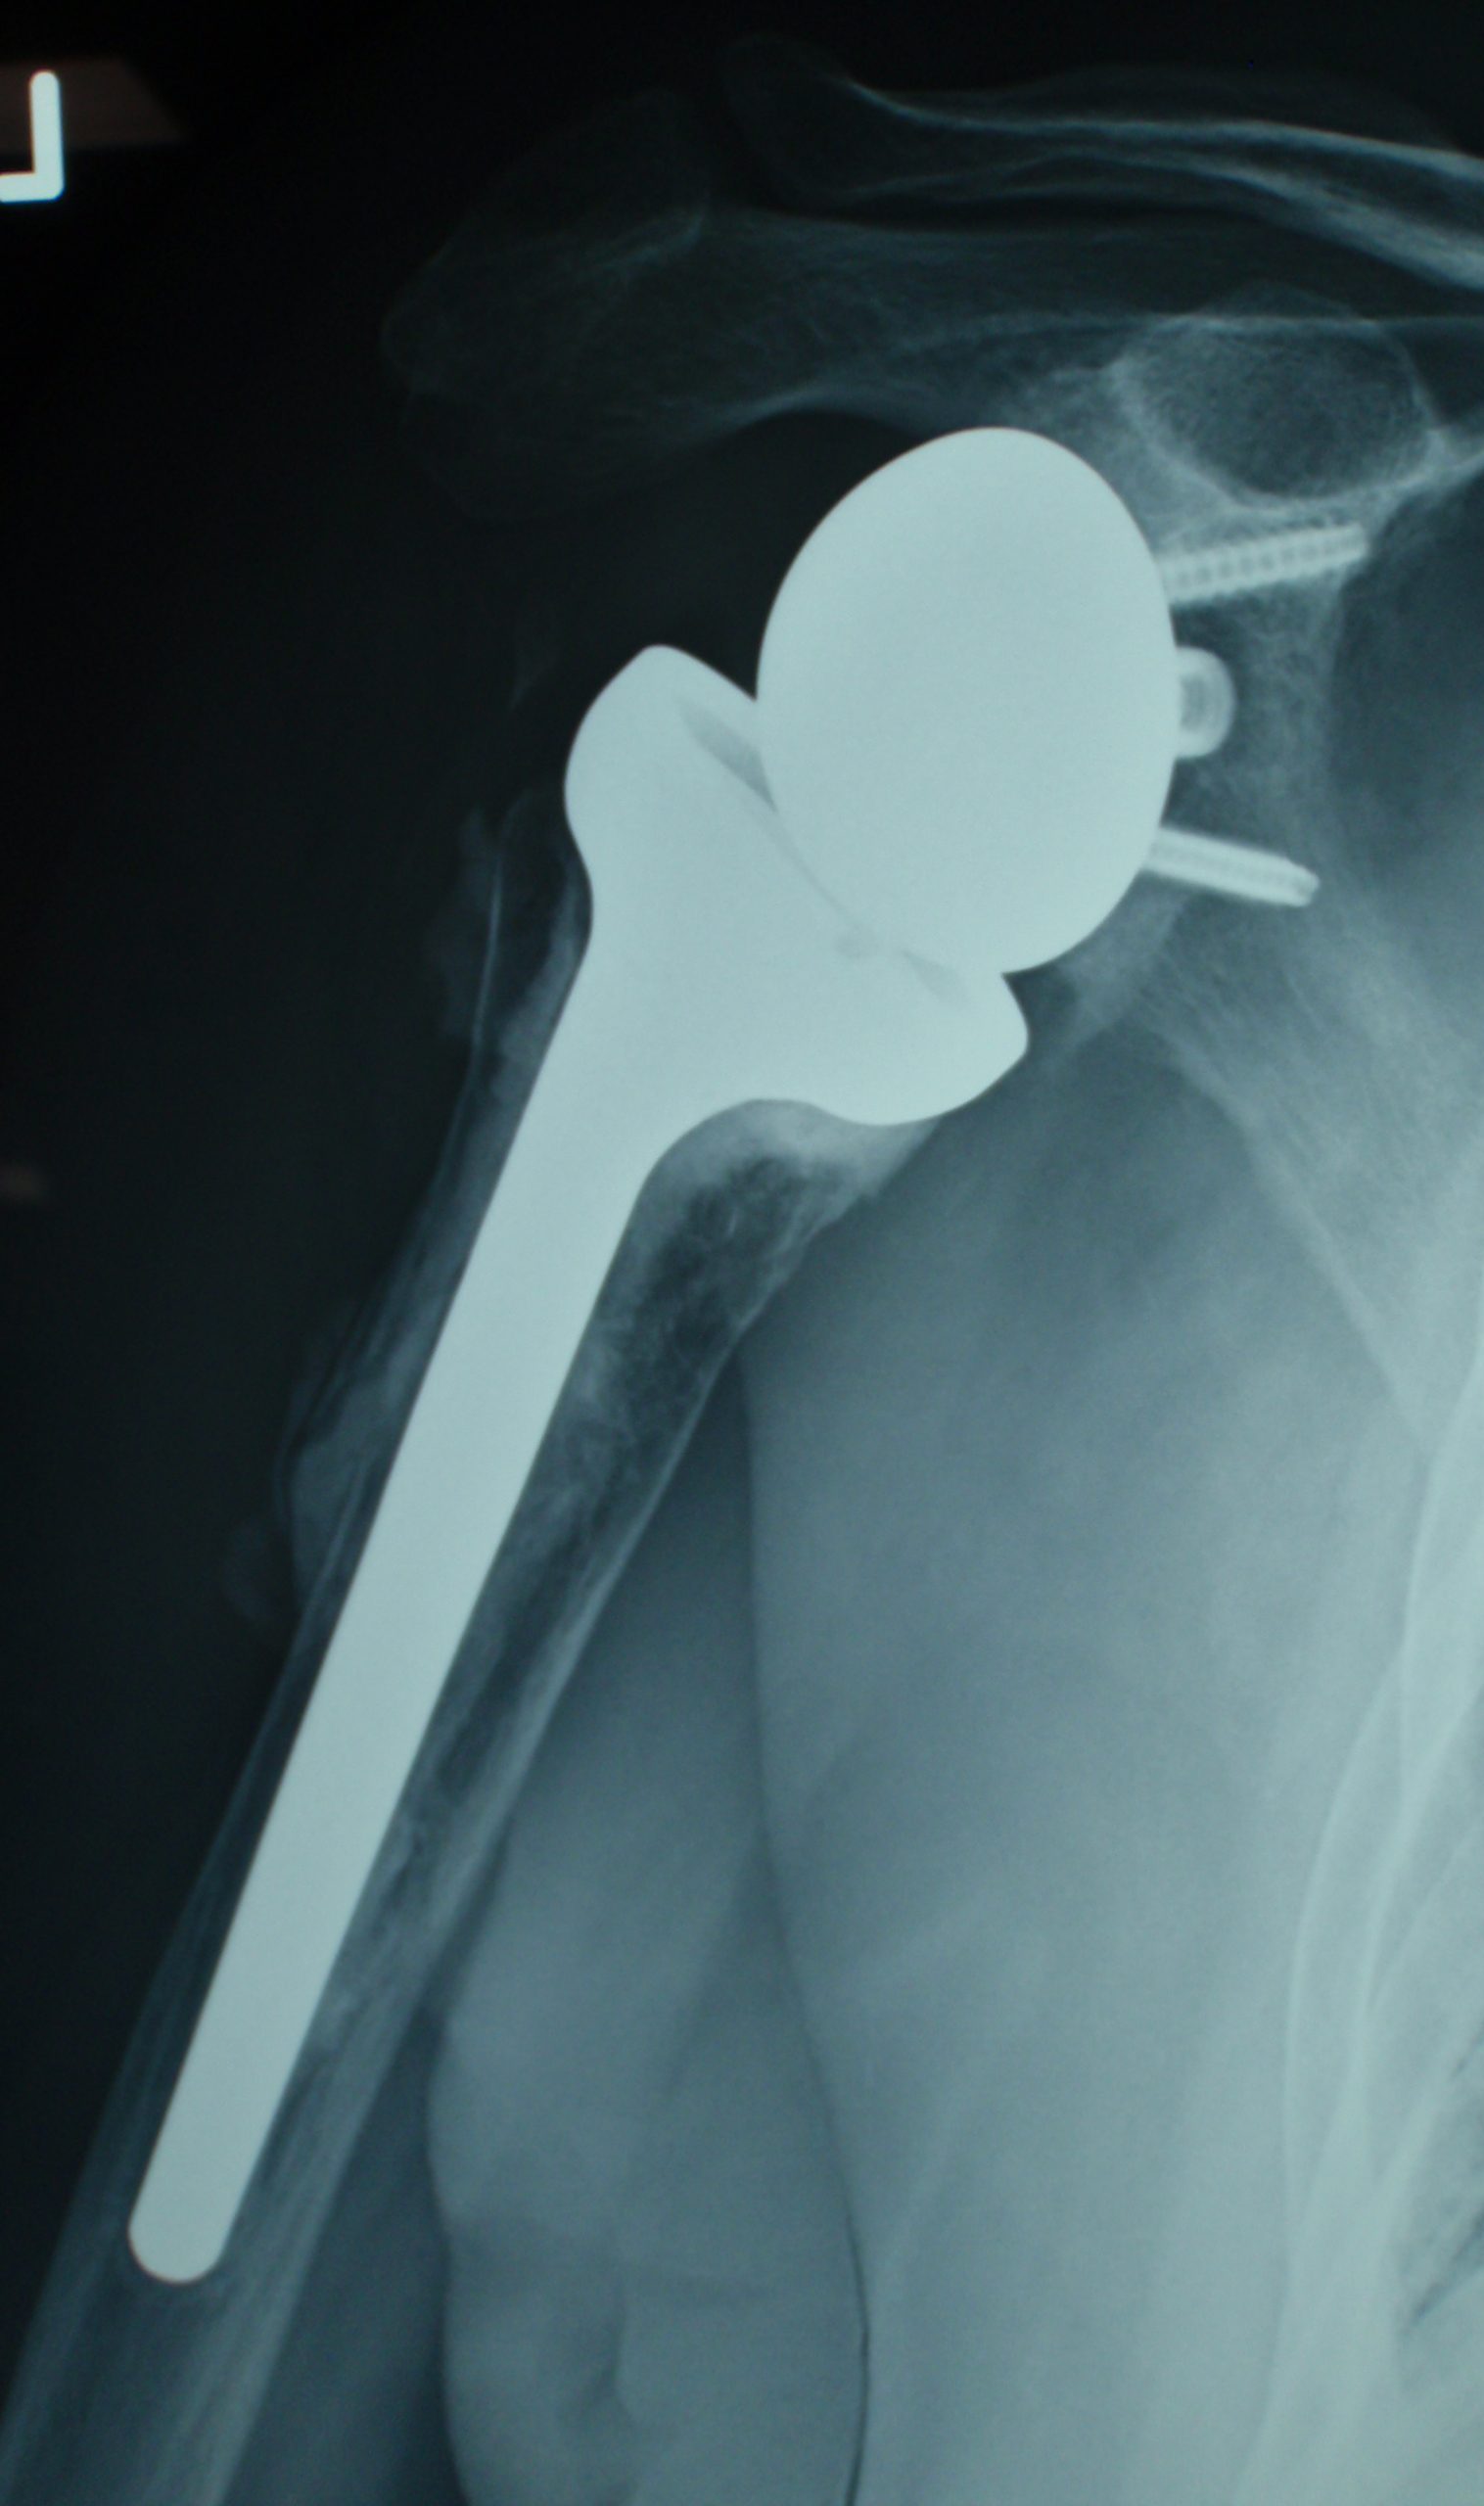

What Is Shoulder Joint Replacement . It is very effective in relieving shoulder pain and is. shoulder replacement surgery involves removing damaged parts of the shoulder bones and replacing them with. shoulder replacement surgery is an operation to replace your damaged shoulder joint with an artificial joint. how long does it take to recover? an orthopedic surgeon will replace the natural bone in the ball and socket of your shoulder joint with a. Shoulder replacement surgery is an increasingly common procedure. You can have a total or. Total shoulder replacement, also known as total shoulder arthroplasty, is the. What is shoulder replacement surgery? shoulder replacement surgery involves removing damaged areas of your shoulder and replacing them with artificial parts. a shoulder replacement is a procedure that tries to eliminate the source of pain and dysfunction by replacing damaged parts of the.

What Is Shoulder Joint Replacement Shoulder replacement surgery is an increasingly common procedure. shoulder replacement surgery is an operation to replace your damaged shoulder joint with an artificial joint. how long does it take to recover? What is shoulder replacement surgery? shoulder replacement surgery involves removing damaged parts of the shoulder bones and replacing them with. shoulder replacement surgery involves removing damaged areas of your shoulder and replacing them with artificial parts. It is very effective in relieving shoulder pain and is. Shoulder replacement surgery is an increasingly common procedure. Total shoulder replacement, also known as total shoulder arthroplasty, is the. You can have a total or. an orthopedic surgeon will replace the natural bone in the ball and socket of your shoulder joint with a. a shoulder replacement is a procedure that tries to eliminate the source of pain and dysfunction by replacing damaged parts of the.